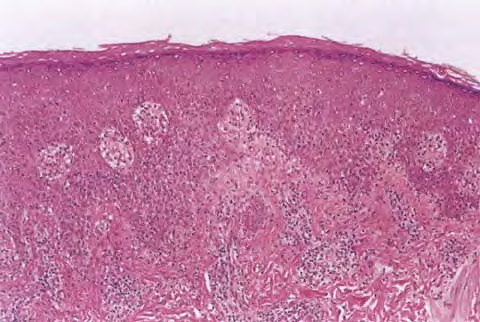

Scondary syphilis = الافرنجي الثانوي